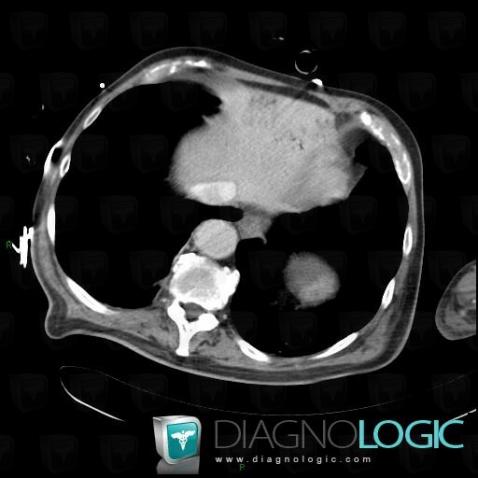

Portal venous gas, Liver, Portal vein and branches, CT

Here is the specific information in the key image above:

- Diagnosis Portal venous gas, Location(s) Portal vein and branches, with gamuts Liver, with gamuts